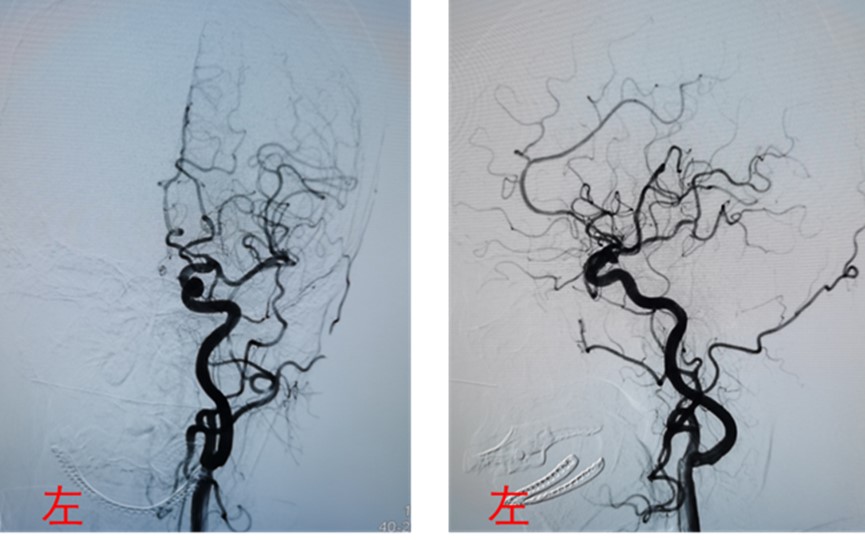

支架置入术的确存支架内血栓形成和术中栓塞的风险,根据患者的临床症状,似乎是左侧大脑中动脉供血区出现了问题,而是行支架置入术的血管是左侧椎动脉,两者不匹配。恰好患者还在手术台上,我们立即复查造影,结果显示左侧椎动脉开口处支架贴壁良好,管腔通畅,椎-基底动脉、左侧大脑中动脉、大脑前动脉主干血管及分支血管显影良好(图2)。排除了支架内血栓形成或术中栓塞的情况。

图2复查DSA显示左侧大脑中动脉、大脑前动脉主干及分支血管显影良好